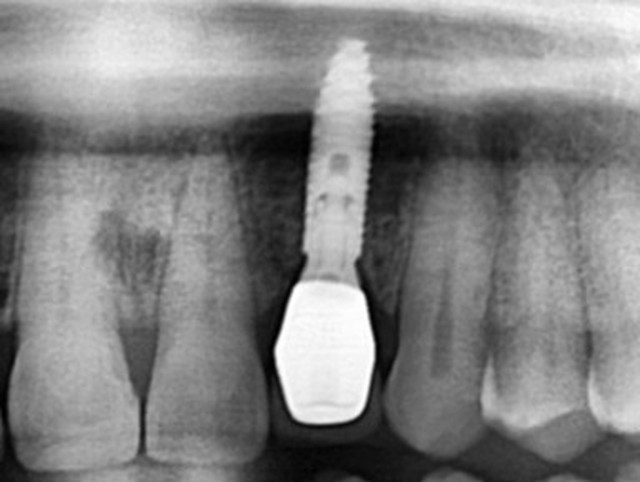

Phục hồi trên implant tại vùng thẩm mỹ như răng thật tại Nha Khoa Như Ngọc (21 Trần quang diệu, Hà Nội).